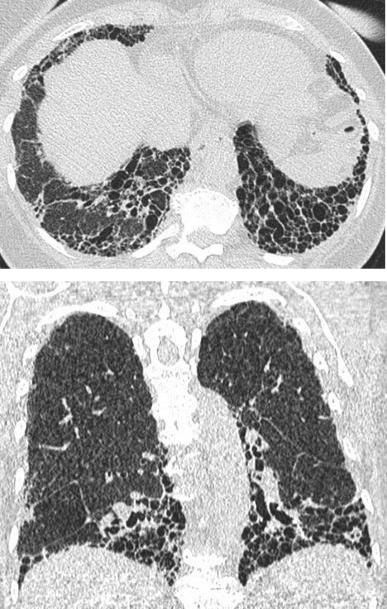

Типичный КТ-паттерн ОИП

Распределение*

Базальное (иногда диффузное) и субплевральное предоминирование

Распределение часто гетерогенное

КТ-признаки

Сотовое легкое

Ретикулярные изменения

Тракционные бронхоэктазы/бронхиолоэктазы

Отсутствие признаков другого ИЗЛ (не-ИЛФ)

*Ассиметрия изменений - до 25: случаев